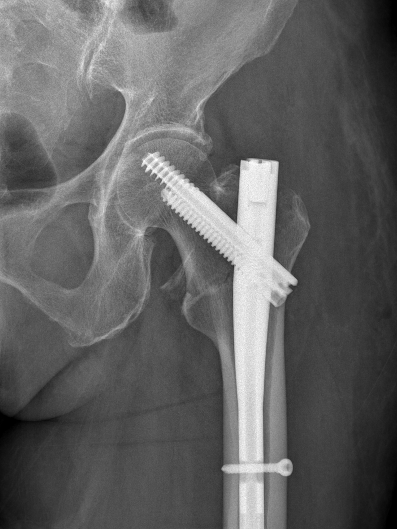

为提升区域内基层医疗机构糖尿病足诊疗服务能力、促进青年医师对糖尿病足的规范化诊治水平,遵义市第二城市医疗集团总院(贵州航天医院)圆满举办贵州省继续医学教育项目——胫骨横向骨搬移技术治疗糖尿病足专题研讨班。 贵州航天医院党委委员、副院长彭亮出席会议并致辞,遵义市第二城市医疗集团各成员单位,以及红花岗区、汇川区、绥阳县、桐梓县等多个区县的基层医疗机构骨干医师参加会议。 研讨班 本次研讨班以胫骨横向骨搬移技术在糖尿病足治疗中的应用为核心主题,围绕糖尿病药物治疗与生活方式管理策略、围手术期血糖精准调控要点、胫骨横向骨搬移技术典型病例深度解析、糖尿病足的临床分型与个体化治疗方案制定等临床实践中的热点与难点展开深入探讨,通过专题授课、案例研讨、互动交流等多元化形式,为参会者搭建了理论与实践结合的学习平台。 此次研讨班不仅为区域内基层医院搭建了学术交流与经验共享的平台,更对推动糖尿病足预防、诊断与治疗的规范化、系统化发展起到了积极作用,有效助力青年医师更新专业知识体系、提升临床技能,为进一步保障区域内糖尿病足患者的健康奠定了坚实基础。 贵州航天医院骨科专家简介 陈明勇 骨一科主任,副主任医师 临床擅长:从事创伤骨科工作约20年,对骨缺损、骨不连、骨肿瘤、肢体畸形等的肢体矫形重建及功能重建,慢性化脓性骨髓炎的根治治疗、糖尿病足的保肢治疗、快速康复理念(ERAS)下的老年骨折的诊治,四肢复杂骨折的诊治,四肢骨折等微创手术治疗具有丰富的临床经验。 2004年毕业于遵义医学院临床专业,曾在中国人民解放军总医院、广西医科大学第一附属医院、上海第六人民医院骨科进修。中国中西医结合学会骨伤科专业委员会横向骨搬移治疗糖尿病足及微血管网再生学组首届委员,遵义市医学会创伤分会常务委员。 瞿 晖 骨科党支部书记,骨二科主任,副主任医师 临床擅长:对骨科的常见病、关节外科、脊柱外科及运动医学疾病的诊治具有丰富的临床经验,熟练掌握骨科手术操作技术。 毕业于遵义医学院临床医学系,2005年前往广州中山大学第一附院骨显微医学部进修学习,2011年前往成都华西医院进修学习,并多次在省内外学习骨科相关知识,是中华医学会骨科分会会员。 赵小锋 中共党员,骨二科副主任,副主任医师 临床擅长:从事骨科临床工作11年,对骨科常见病、多发病诊疗有较为丰富的临床经验,擅长脊柱相关疾病诊断及治疗,尤其是颈、腰、腿疼痛疾病诊断及治疗,擅长胸腰椎骨折微创经皮穿刺内固定术、经皮穿刺椎体成形术、经皮穿刺脊柱内镜下腰椎间盘摘除术、单纯开创腰椎间盘摘除术、腰椎滑脱复位椎间植骨椎融合内固定术、腰椎管狭窄减压融合内固定术及人工髋、膝关节置换术等。 2012年毕业于遵义医学院外科学专业硕士研究生,2019年参加“遵义市115医学人才精英计划”于上海交通大学第一附属医院培训学习,2023年于北京大学第三人民医院脊柱外科进修学习,曾获得遵义市优秀医师荣誉称号。 遵义市手外科第一届委员,遵义市医学会创伤分会第一届委员,遵义市医学会创伤分会第二届委员,贵州省康复医学会第三届脊柱脊髓专业会委员,遵义市医学会烧伤与整形外科学分会委员,发表论文5篇,其中国家级核心期刊1篇,SCI论文1篇,主持市级课题1项并结题,参与市级课题2项。 赵兴东 骨科主任医师 临床擅长:擅长骨科的常见病及各种创伤、四肢骨折创伤修复、骨感染、手足疾病的诊治和手足体表畸形的矫形整复,熟练掌握骨科四肢骨病及创伤的手术操作技术,尤其在四肢关节复杂性损伤、手足外伤、组织缺损创面、难治创面的皮瓣修复方面及平足、高弓足矫形方面及四肢慢性疼痛诊治、康复方面具有丰富的临床经验。 硕士研究生,毕业于遵义医学院临床外科系,2015年前往山东省立医院手足外科进修学习;遵义市医学分会创伤分会第一、二届委员,遵义市手外科医学会第二委届员会常务委员;在省级及省级以上期刊发表文章9篇,参编著作2部,参与主持并完成市级课题1项,参与市级课题2项、省级课题1项。 张艳金 中共党员,骨科副主任医师 临床擅长:从事骨外科工作16年,对复合伤、多发伤的救治、四肢骨干骨折、关节周围骨折、骨肿瘤、骨髓炎等诊治具有丰富的临床经验。 中共党员,硕士研究生,2006年本科毕业于山西医科大学第二临床医学院,2011年研究生毕业于北京军区总医院;在“老年COPD患者合并髋部骨折的诊治”国际合作课题组研究两年,在老年髋部骨折的诊治方面具有丰富的经验,并发表论文6篇;主持遵义市级课题1项,承担遵义医科大学的临床教学工作,获得遵义医科大学优秀带教老师荣誉。编撰有《骨科疾病诊疗精粹》一书,开展2项新技术,编撰地方规范《务川自治县创伤骨科常见疾病诊疗规范》一书。 张俊凯 骨科副主任医师 临床擅长:从事骨科临床工作28年,对创伤骨折、骨感染、骨缺损、骨不连等外科诊治,四肢骨折的微创手术治疗,四肢复杂骨折(如关节内粉碎性骨折、多发骨折等)的损伤控制及手术治疗等具有丰富的临床经验。 1995年毕业于遵义医学院临床专业,2009年前往复旦大学附属医院骨科进修1年。 卢懿明 中共党员,骨科副主任医师 临床擅长:从事骨科工作18年,对创伤骨折、四肢骨折的微创手术治疗、四肢复杂骨折(如关节内粉碎性骨折、多发骨折等)的损伤控制及手术治疗,尤其是髋部骨折的PFNA等微创技术,踝关节骨折、膝关节周围骨折的Mipo微创技术等具有丰富的临床经验,开展了4项新技术,发明6项新型专利技术。 2005年毕业于遵义医学院临床专业,2017年,前往南方医科大学第三附属医院骨科进修半年,回院后运用Mipo技术对骨干骨折及干骺端骨折的治疗技术,同时积极开展骨盆骨折、髋臼骨折腹直肌外侧切口的应用;发表了多篇专业论文,经常参与省内外学术交流会授课,获得医院荣誉称号多个。 邬夏荣 骨科副主任医师 临床擅长:从事骨科工作16年,对四肢复杂骨折、骨肿瘤的诊治,尤其是足踝创伤、慢性踝关节损伤、平足症等诊疗具有丰富的临床经验。 2006年毕业于遵义医科大学临床医学专业,曾在陆军军医大学西南医院进修学习,发表多篇骨科学术论文。 余德怀 中共党员,骨科副主任医师 临床擅长:从事骨科工作10余年,对运动医学、骨关节、脊柱外科常见病、多发病的诊治具有丰富的临床经验。 硕士研究生,2011年毕业于遵义医学院临床医学专业,曾前往遵义医科大学附属医院运动医学专业进修学习;是贵州省医学会运动医学分会青年委员,西部关节镜联盟委员;发表多篇骨科学术论文。 冯 乾 骨科副主任医师 临床擅长:从事骨科工作近20年,熟练掌握骨科多发病及常见病的诊治,尤其对脊柱退变性疾病的诊断及治疗具有丰富的临床经验,主要研究脊柱微创相关治疗方式,能熟练开展椎间孔镜及UBE。 曾前往北京大学第三医院进修学习疼痛及椎间孔镜、首都医科大学友谊医院专业进修脊柱内镜;是贵州省康复医学会第三届脊柱脊髓专业委员会委员;发明专利3项、发表脊柱外科专业论文多篇。 贵州航天医院骨科简介 基本情况 贵州航天医院(原3417医院)骨科组建于1968年,前身是以创伤和断肢(断指)再植闻名于世的上海市第六人民医院骨科,中国断肢(断指)再植的奠基者、中科院院士陈仲伟等专家莅临科室指导医疗和教学,并在70年代开展了贵州省首例断肢(断指)再植手术。组建50余年来,诊治患者已逾百万,挽救了无数的伤病员,成为了保障遵义地区人民群众健康的重要支撑。 经过几代人的不懈努力,今天的骨科,已由创伤骨科发展至骨病、骨肿瘤、骨结核等领域,现有脊柱外科、关节外科、四肢创伤、手足外科四个亚专科,成为了集医疗、教学、科研于一体的综合学科,是贵州省临床重点专科、遵义市临床重点专科、遵义市骨科临床医学中心、遵义市基层骨科专科联盟理事长单位。 科室目前开放床位110张,共有医护人员50余人,副高级以上专家18人,硕士研究生15人。拥有一流骨科医疗设备多台,每年不定期选派优秀技术骨干到全国各大知名医学院校进修、学习、参观、交流,并邀请国内、国外知名专家教授来院进行交流、指导,通过不断引进国内外先进的诊疗技术,科室医疗技术水平稳步提升,为广大人民群众提供了优质的医疗服务。 专科特色 骨一科 (一)骨缺损、骨不连的肢体与功能重建 胫骨横向骨搬移技术治疗糖尿病足: (二)慢性骨髓炎的根治治疗 (三)肢体缺血性疾病如糖尿病足、脉管炎的保肢治疗 (四)皮瓣修复 (五)复杂创伤的治疗 (六)老年髋部骨折及小儿骨折快速手术 老年髋部骨折: 骨二科 (一)胸腰椎骨折微创经皮椎弓根螺钉固定术 (二)老年性骨质疏松性患者腰椎滑脱脊柱内固定术(骨水泥螺钉) (三)V形双通道脊柱内镜技术(VBE)腰椎融合术治疗腰椎退行性疾病 (四)老年性骨质疏松性骨折(PVP/PKP)术 (五)人工髋关节置换术 (六)双侧股骨头坏死人工全髋关节置换 (七)右侧全髋置换术后假体周围骨折翻修 (八)人工膝关节置换术 (九)人工膝关节假体松动翻修 (十)关节镜技术 传统手术切口 关节镜技术切口 诊疗范围 骨一科 1.四肢创伤、矫形。 2.手、足踝外科。 骨二科 End